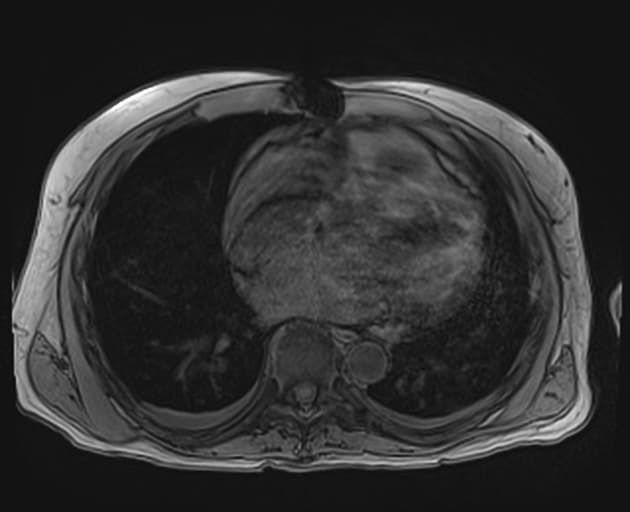

Axial T1 fat sat

MRI•Axial T1 fat sat•1 Img

- T1 FS: tổn thương giảm tỷ trọng ở trung tâm, tại/gần cửa gan (porta hepatis). Không thấy tăng quang đáng kể sau tiêm thuốc cản quang.

- "Việc không tăng quang rõ rệt và giãn ống mật phía trên đoạn hẹp đường mật trung ương rất gợi ý ung thư ống mật."

Ung thư ống mật tế bào gan vùng cửa gan, còn gọi là u Klatskin, là khối u ác tính xuất phát từ biểu mô của các ống mật gần, đặc biệt tại vị trí nối ống mật gan phải và trái. Bệnh thường khởi phát âm thầm với các triệu chứng không đặc hiệu như vàng da, ngứa, sụt cân, gây khó khăn trong chẩn đoán. Trên hình ảnh, tổn thương điển hình là khối u vùng cửa gan gây giãn ống mật theo phân thùy, với dấu hiệu 'cắt cụt' trên chụp đường mật. MRCP rất nhạy trong việc xác định mức độ và phạm vi tắc mật. Trên MRI có tiêm thuốc, khối u thường giảm tín hiệu và tăng quang kém trên các dãy T1 và T2. Việc phân biệt với các đoạn hẹp lành tính, đặc biệt trong viêm đường mật xơ hóa tiên phát, có thể khó khăn và cần sinh thiết hoặc đánh giá nội soi. Chẩn đoán sớm rất quan trọng để xem xét cắt bỏ phẫu thuật hoặc ghép gan, mặc dù phần lớn các trường hợp khi chẩn đoán đã không còn khả năng cắt bỏ.